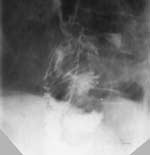

Прямым признаком являлся затек контрастного вещества за пределы исследуемого органа (Рис. 1, 2). Этот симптом на определенных стадиях развития процесса может наблюдаться у всех больных. Выделяют медиастинальный и плевральный затек. Диагностика начальной фазы медиастинального затека сложна. В ряде случаев он выявляется в виде остроконечного выступа в зоне анастомоза. В последующей динамике образуется скопление контрастного вещества в виде бесформенного кармана, ориентированного, как правило, в каудальном направлении. Надо отметить, что диагностика затека, ориентированного перпендикулярно или наклонно к зоне анастомоза, не составляла труда, тогда как выявление распространения контрастного  вещества вдоль стенки желудка или кишки представляло определенные сложности. Таких больных, если позволяла клиническая ситуация, мы осматривали в динамике через несколько часов, когда пищеварительный тракт освобождался от контрастного вещества, а в области затека оно оставалось. При тяжелом состоянии больного и невозможности динамического наблюдения  в экстренном порядке таким больным выполнялась компьютерная томография органов грудной клетки. На компьютерных томограмах  было легче определить, где находится контрастное вещество: вне или внутри пищеварительного канала. Таким образом, удавалось вовремя диагностировать несостоятельность швов анастомоза.

Рис. 2. Медиастинальный затек с образованием горизонтального уровня.